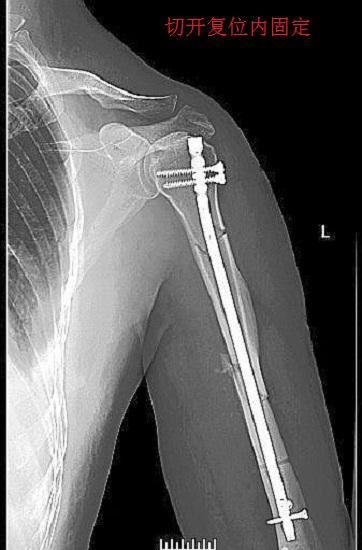

1、治疗手段。肱骨头骨折后的手术治疗,通常都要采用“切开复位内、固定”的外科手段。所谓切开复位内固定,是指将软组织切开,在骨折部位完全暴露的情况下进行复位,并采用牢靠的方法进行固定(例如:打钢钉、接骨板等),最后再将软组织缝合。切开复位内固,定的治疗方法具有复位精准、固定可靠的优点,但也会因为大范围的手术创口给肌肉、皮肤甚至神经组织的愈合带来新问题。2、适应证。手术治疗适用于骨折移位严重的非稳定性骨折、合并重要的血管或神经损伤者、有软组织嵌入骨骼的骨折、体形肥胖者的肱骨骨折(难以通过软组织实施复位和固定)、手法复位失败者、外固定不可靠者、青壮年的陈旧性骨折等情况。